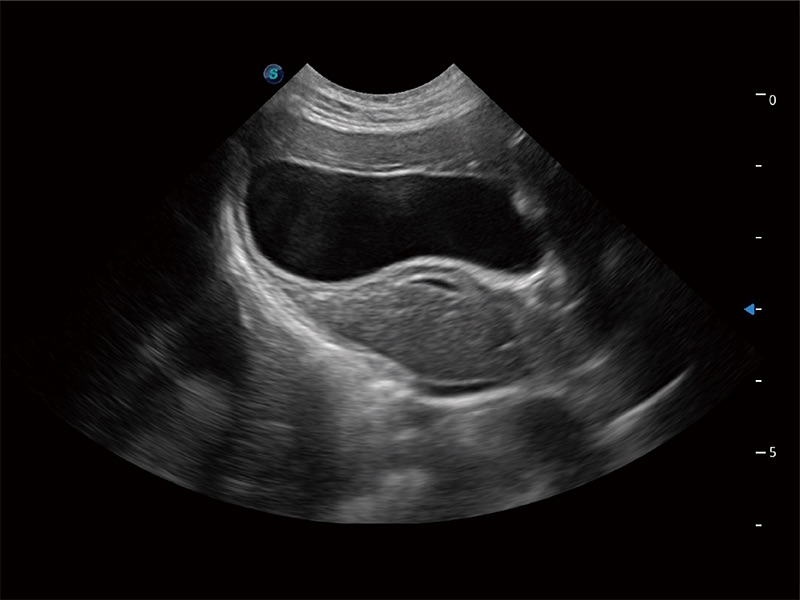

高性能和先進(jìn)的臨床應(yīng)用工具可以為動物醫(yī)生提供臨床信心。ProPet 80 搭載了先進(jìn)的腹部和淺表應(yīng)用工具,幫助醫(yī)生在日常臨床實(shí)踐中發(fā)揮前所未有的作用。

操作簡便,無需高頻度外力作用即可真實(shí)反映組織的形變,快速評估腫瘤良惡性。

非線性融合造影成像充分利用諧波和基波信號,為難以觀察的血流進(jìn)行增強(qiáng)顯像??捎糜诰€陣、凸陣、微凸陣、相控陣探頭。